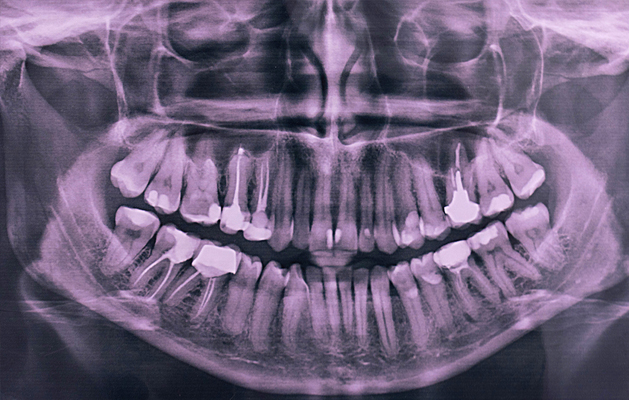

Best Clinical Dental X-ray in Chennai

Panoramic x-rays show the entire mouth area — all the teeth in both the upper and lower jaws — on a single x-ray. This x-ray detects the position of fully emerged as well as emerging teeth, can see impacted teeth, and help diagnosis tumors.